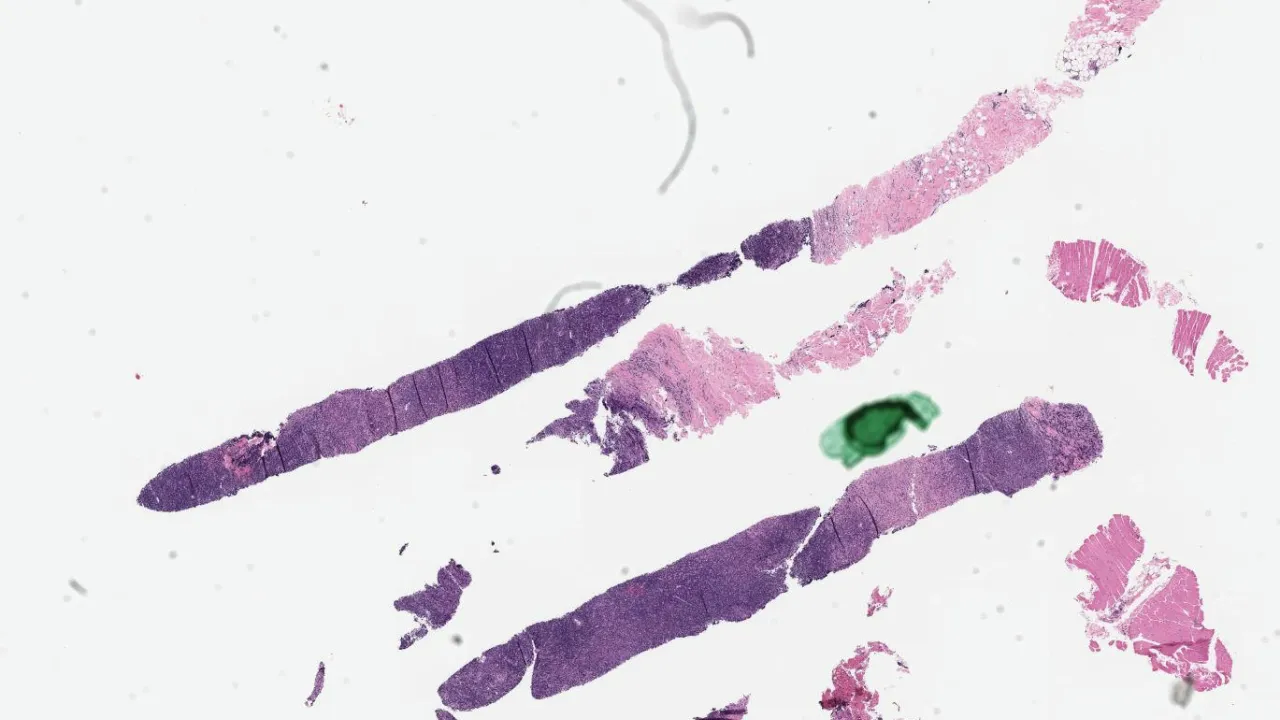

Soft Tissue, Subcutaneous panniculitis-like T-cell lymphoma, CD8 stain